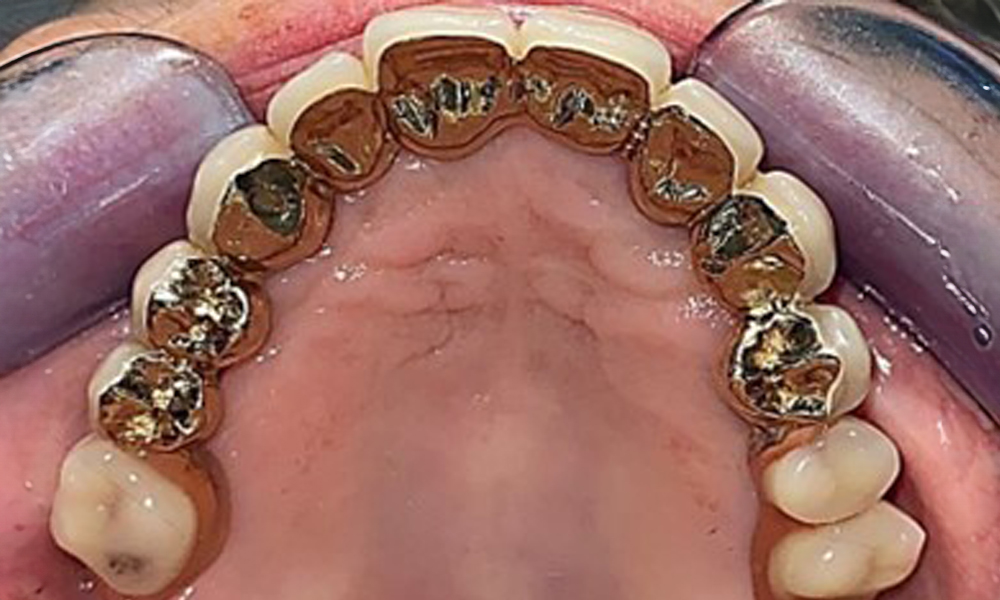

The patient was fitted with a combined removable maxillary telescopic prosthesis more than 25 years ago (Fig. 1, Fig. 2, Fig. 3) and is very happy with her dentures. The patient has an adequate fixed denture for the mandible (Fig. 4).

The dental findings are as follows: Combined removable implant and tooth-supported telescopic prostheses on implants 15, 13, 21, 23, 24, 25 and tooth 11 (Fig. 1, Fig. 2, Fig. 3). The patient was fitted with a fixed mandibular denture. Adequate bridges were present over 37 to 34 and 45 to 47 (Fig. 4), the crown margins were intact and there were no active caries. A composite filling with a marginal gap was present on tooth 43. There was mandibular gingival recession, exposing 1 to 3 mm of root surface. This also applies to 11.